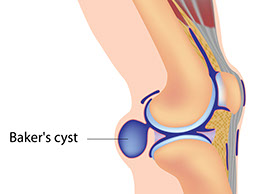

Baker’s Cyst

Signs & Symptoms

Painless or painful swelling behind the knee. May feel like a water-filled balloon.

What to Do

Call doctor.